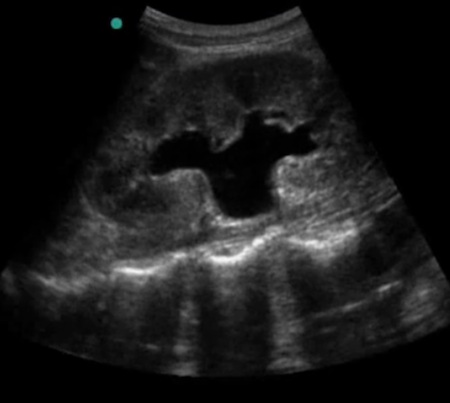

Fot. Obraz wodonercza prawostronnego w USG

Wodonercze jest wskazaniem do diagnostyki urologicznej. Konieczne jest ustalenie jaka jest przyczyna wodonercza i w zależności od rozpoznania planuje się dalsze leczenie. Wśród najczęstszych przyczyn wodonercza wymienia się kamicę moczowodową, zwężenie połaczenia miedniczkowo - moczowodowego i schorzenia powodujące ucisk na moczowód. W celu ustalenia rozpoznania wykonuje się urografię lub tomografię komputerową. Jeśli urolog stwierdzi wskazania do odbarczenia nerki wówczas zakładany jest nefrofix lub cewnik moczowodowy.